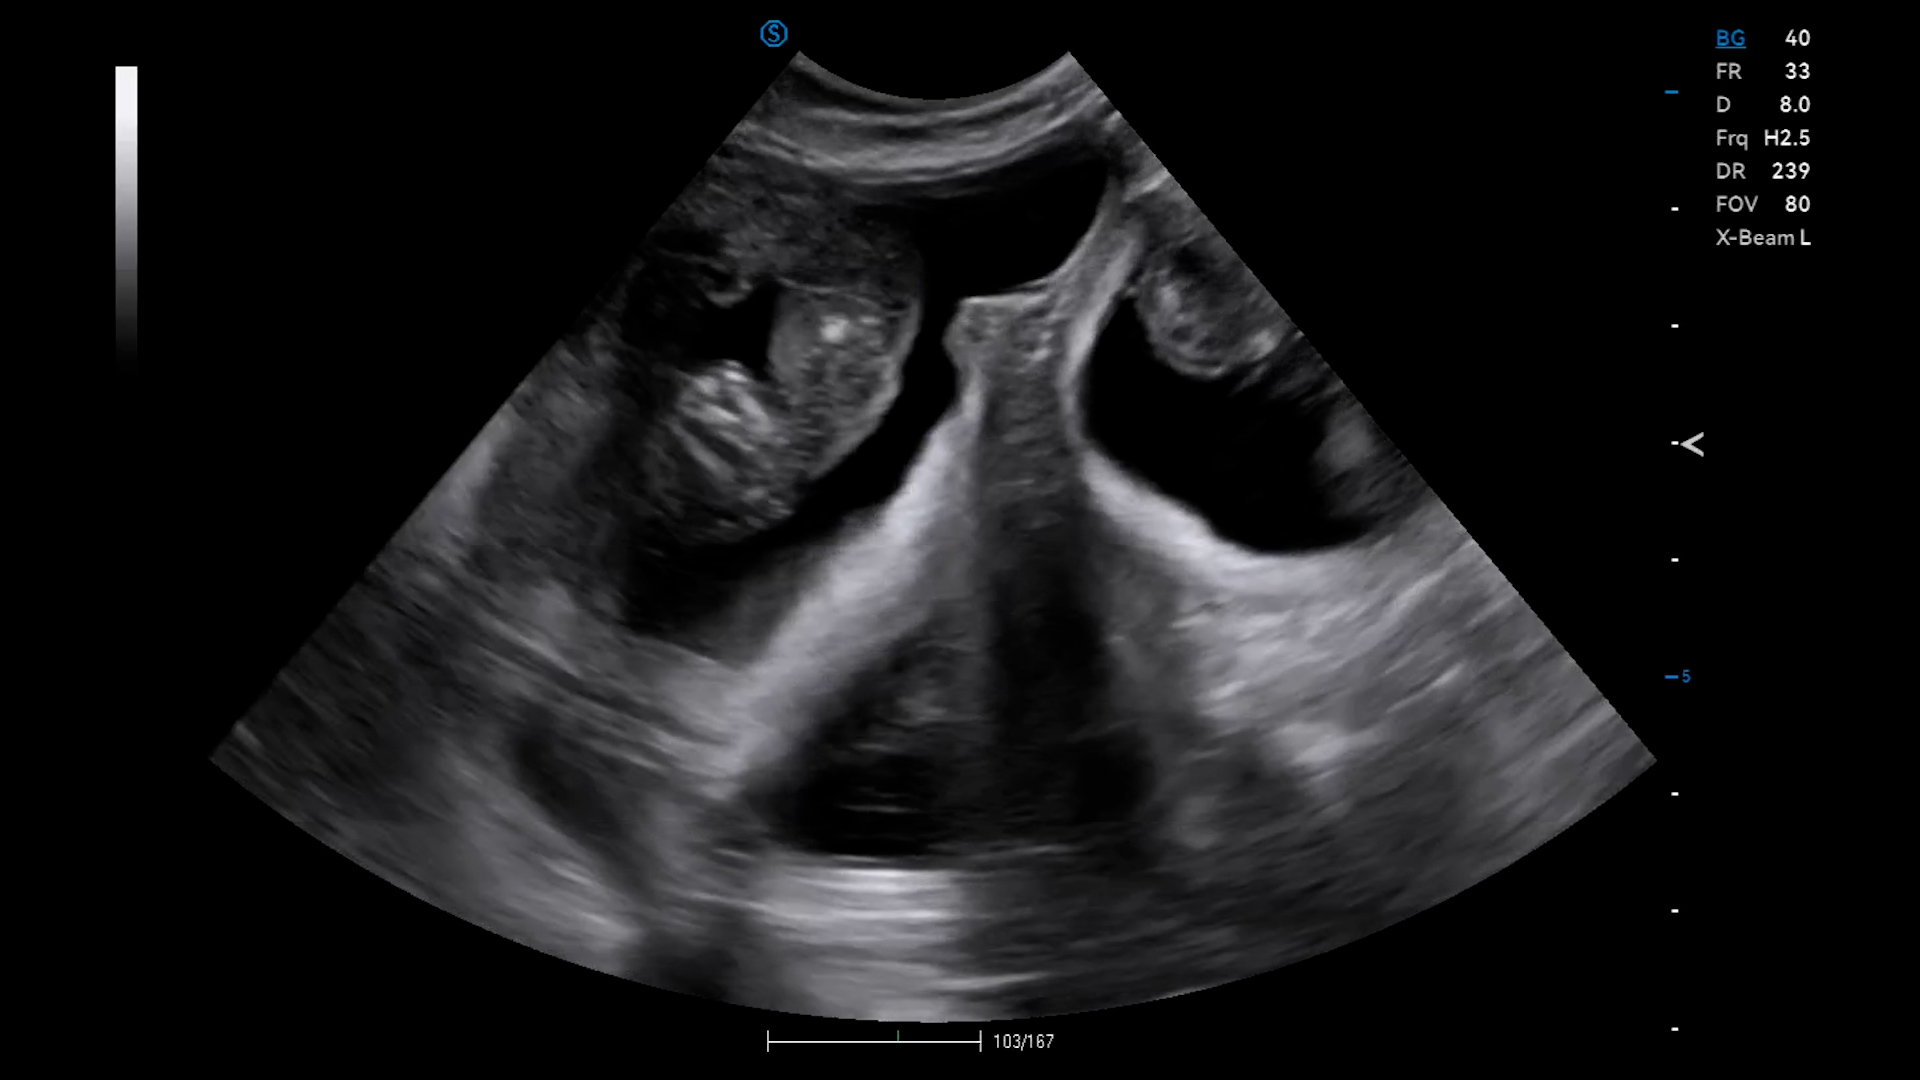

We confirmed 8 pregnancies today in Maidstone, Kent. Most of them were between 50 – 70 days, and it is surprising how tiny the foetus still is even at that